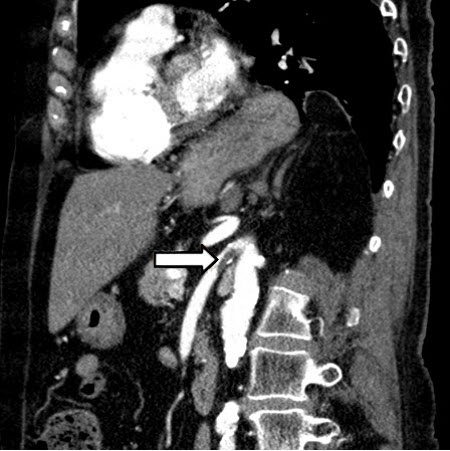

Abscesso hepático: tomografia computadorizada (TC) (vista coronal) mostrando abscesso hepático em um homem de 46 anos de idade que apresentava febre, fadiga e tosse

Do acervo de imagens radiológicas do Massachusetts General Hospital